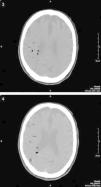

TC cráneal sin contraste realizada 6h después del procedimiento colangioendoscópico y el inicio de la sintomatología. Los cortes tomográficos realizados en ambos centros semiovales muestran la existencia de múltiples imágenes redondeadas de baja densidad compatibles con múltiples burbujas aéreas intraarteriales distribuidas a lo largo del territorio vascular de la arteria cerebral media derecha. Comienzan a observarse los signos precoces típicos de un accidente isquémico agudo con pérdida de la diferenciación corticosubcortical y tenue hipoatenuación del hemisferio cerebral derecho producidas por émbolos gaseosos.

Durante la dilatación, el paciente presenta una súbita disminución del estado de alerta con discreta desaturación, por lo que se detiene el procedimiento y se aplica oxígeno al 100% mediante mascarilla nasal. Ya en planta, el paciente se encuentra consciente y orientado, y tras la realización de una exploración neurológica básica se observa una disminución de la fuerza del hemicuerpo izquierdo. Ante la sospecha de ictus cerebral se solicita consulta urgente al Servicio de Neurología, que confirma estos hallazgos; éste, a su vez, solicita una TC urgente (figs. 3 y 4).

La TC urgente muestra la presencia de múltiples burbujas distribuidas a lo largo del territorio vascular de la arteria cerebral media derecha con pérdida de la diferenciación corticosubcortical e hipodensidad generalizada de todo el hemisferio derecho con respecto al lado contralateral compatible con externo infarto agudo de todo el territorio de la arteria cerebral media derecha secundario a múltiples émbolos gaseosos.